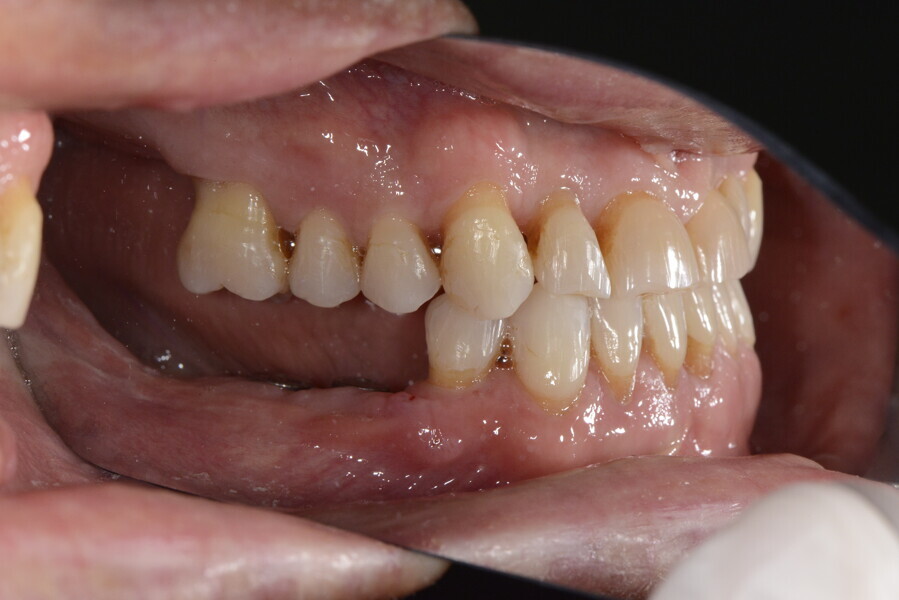

The 58-year-old patient wished to improve his oral aesthetics and function, complaining of mobility of the posterior teeth and wear of the anterior teeth. After data collection, a very complex situation was identified (Figs. 11–13):

1. severe periodontitis with poor prognosis of some teeth;

2. anterior crossbite;

3. severe wear mainly of the anterior teeth and compensatory eruption;38

4. atypical swallowing and lower posture of the tongue at rest;

5. masticatory dysfunction during the mastication test; and

6. no significant signs of temporomandibular disorder.